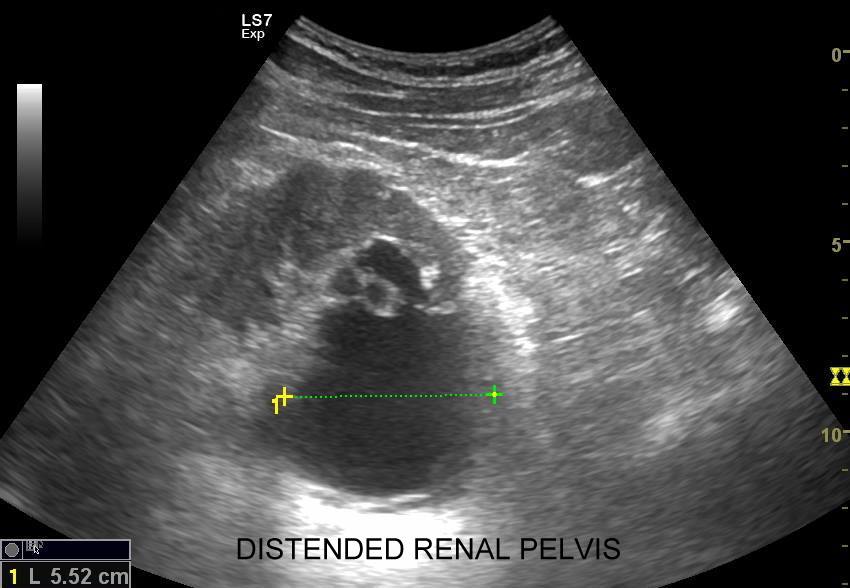

Objawy kolki nerkowej wynikają z mechanicznego drażnienia i wtórnego ranienia ścian moczowodu w trakcie przemieszczania się kamienia, a ich lokalizacja zależy od miejsca, w którym aktualnie złóg się znajduje. Najczęściej może on utknąć w naturalnych zagięciach i przewężeniach moczowodu, tj. na złączu miedniczkowo-moczowodowym, na skrzyżowaniu moczowodu z naczyniami biodrowymi oraz przy pęcherzu moczowym. W omawianych warunkach dominują zasadniczo bóle o charakterze ostrym. Druga przyczyna objawów związanych z kolką nerkową wynika z zastoju moczu oraz podwyższonego ciśnienia w układzie kielichowo-miedniczkowym; w tym wypadku dominują bóle tępe.

Badania obrazowe służące wykrywaniu kamicy moczowej to badanie RTG, CT, lecz przede wszystkim badanie USG. W badaniu USG nerek w prezentacji B kamica nerkowa widoczna jest w sytuacji, gdy złogi są odpowiednio uwapnione, odpowiednio duże oraz nie zlewają się z zatoką tłuszczową miedniczki nerki. Zasadniczo złogi w trybie B będą widoczne wyraźniej, gdy położone są w miąższu nerki; z kolei w miedniczce nerkowej, gdy są na tyle duże, że dają artefakt cienia. Czasem w celu uwidocznienia złogu przydatne jest wyłączenie wspomagania typu x-beam.